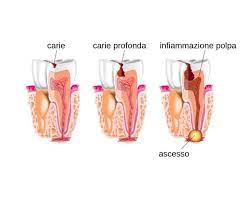

Il trattamento endodontico diventa necessario quando la polpa, parte interna del dente, è infiammata o infetta per cause che possono essere di vario genere (carie molto profonde o da un trauma).

La polpa dentaria è un tessuto molto particolare dei nostri denti e altamente specializzato che negli adulti ha la funzione di percepire il caldo e il freddo principalemnte mentre nei bambin ha il compito di costituire la dentina. Nel caso in cui è presente una carie non curata con prontezza che arriva ad ingrandirsi ed estendersi fino a raggiungere proprio la polpa; il “canale” creatosi viene sfruttato dai batteri per arrivare nella zona interna del dente e causare danni irreversibili. E’ quindi inevitabile una cura endodontica che ha lo scopo di conservare il dente ed evitarne la sua estrazione.

Per evitare di arrivare a questo tipo di interventi è quindi imporatante agire tempestivamente nella cura delle carie fin dall’inizio della loro genesi e per questo è necessario effettuare dei controlli periodici dal proprio dentista.